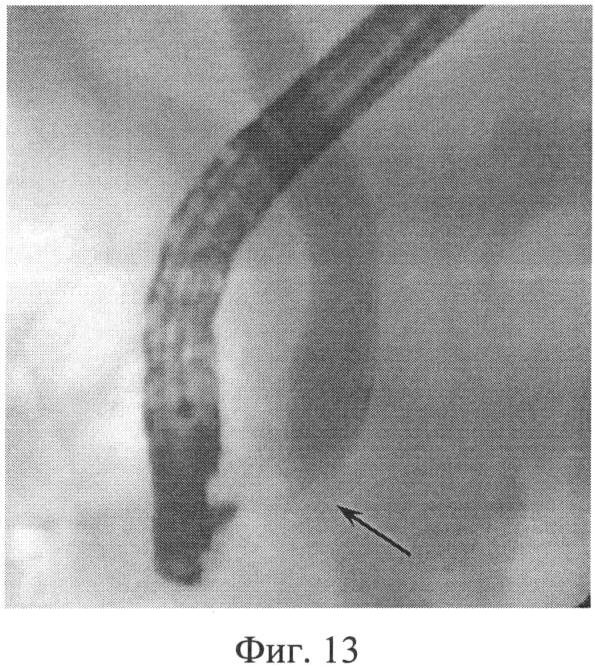

Фиг.12 – после поперечного разреза канюляция пересеченной трубчатой структуры (узкий холедох) успешна, что подтверждается фиг.13.

Фиг.13 – холангиопанкреаторентгенограмма, на которой отчетливо видна одна из причин технических трудностей первичного контрастирования ОЖП – сужение и негомогенность терминального отдела (показано черной стрелкой).